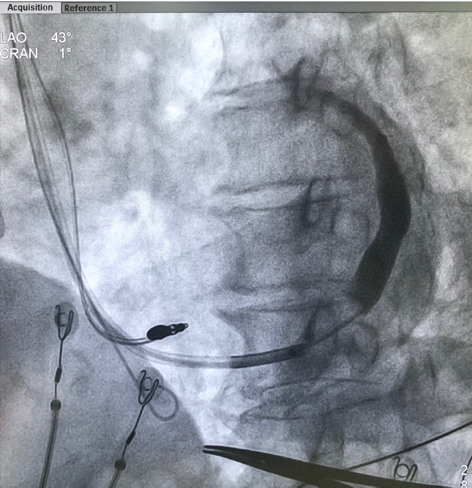

术中通过冠状窦电极将左室递送鞘置入冠状窦,用造影球囊进行造影,尝试寻找合适靶静脉放置左室电极,但造影结果发现血管光溜溜,未能发现明显侧枝静脉。尝试后退球囊在窦口附近再次造影,窦口附近疑似存在微小侧枝,但分支过于细小用PCI导丝进行尝试20分钟未能进入侧枝静脉。

术中手术过程